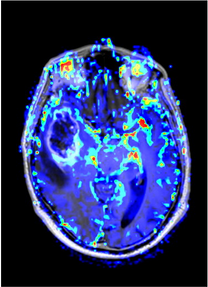

Tratamiento y cirugía de tumores cerebrales

Los avances tecnológicos en Neuronavegación 3D, imagen intraoperatoria, mapping cerebral que incluye la monitorizacion intraoperatoria y cirugía en el paciente despierto y el uso de microscopios de última generación permiten la realización de estas intervenciones con una excelente tasa de éxito.